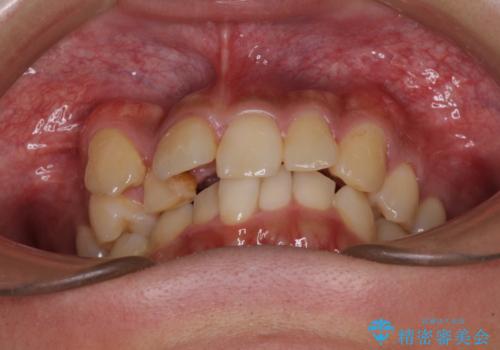

- 上顎の八重歯と正中のズレを気にして来院された患者様です。

八重歯による叢生は著しく、それにより上顎の正中が大きく右にずれている状態でした。

口元の突出感は感じていなかったことと、奥歯の咬み合わせを考慮し、上顎のみ左右の第一小臼歯を抜歯してワイヤー装置にて矯正治療を行うこととしました。